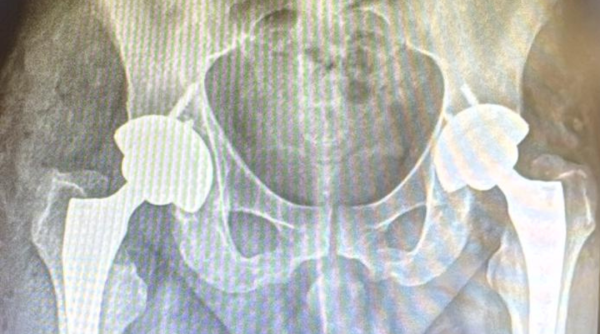

Hospital Ouro Branco realiza duas artroplastias totais de quadril inéditas no mesmo ato operatório

Enquanto em grandes centros urbanos esse tipo de procedimento geralmente demanda a atuação simultânea de duas equipes médicas, a operação ocorreu em 2 horas e 30 minutos e foi executada por apenas uma